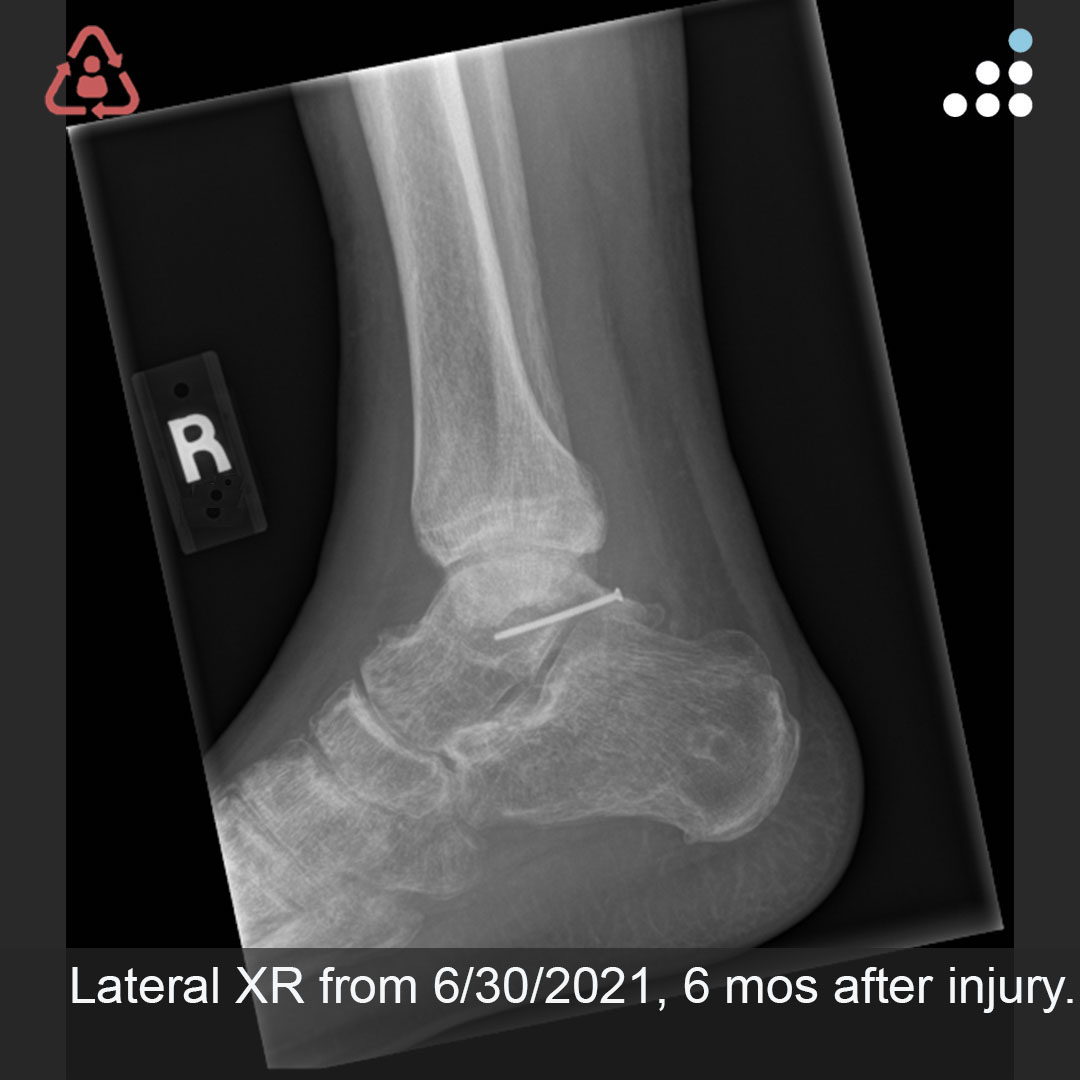

Here is a new case by Dr. Jan Szatkowski (@orthotraumamd) and @IU_Health.

ANKLE PAIN 9 MONTHS S/P OPEN ANKLE FRACTURE-DISLOCATION IN 33M

How would you manage this #orthotwitter?

Vote on this case for CME: orthobullets.tiny.us/yck7hwem